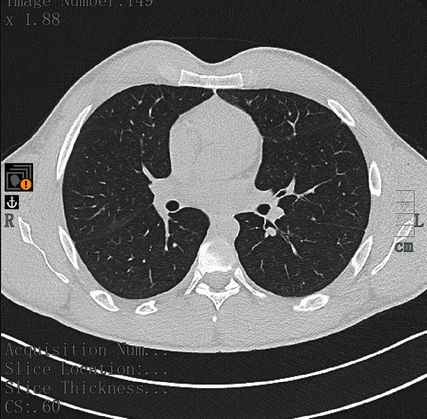

Während des stationären Aufenthaltes hatte der junge Patient keinen neuerlichen blutigen Auswurf. Vor einer geplanten Bronchoskopie mit Biopsie erfolgte eine neuerliche Thorax-CT, wobei sämtliche Konsolidierungen vollständig rückläufig waren (Abb. 2). Mögliche Differenzialdiagnosen waren an diesem Punkt entweder ausgeschlossen oder erschienen als sehr unwahrscheinlich. Es musste daher eine andere Genese geben.